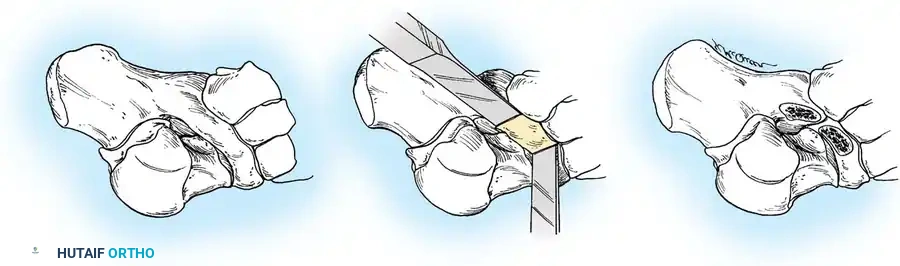

جراحة إزالة التحام الكاحل والعقب

تُجرى هذه العملية عادة للمرضى الأصغر سناً (10 إلى 15 عاماً) عندما يكون الالتحام في المفصل الأوسط (Middle Facet) صغيراً (أقل من 50% من مساحة المفصل) ولا توجد علامات على خشونة المفاصل.

يتم الدخول جراحياً من الجهة الداخلية للقدم، ويتم استئصال الجسر العظمي بدقة باستخدام أدوات دقيقة حتى يظهر الغضروف السليم للمفصل. كما هو الحال في الالتحام السابق، يتم وضع نسيج دهني أو شمع عظمي لمنع الالتصاق مجدداً.